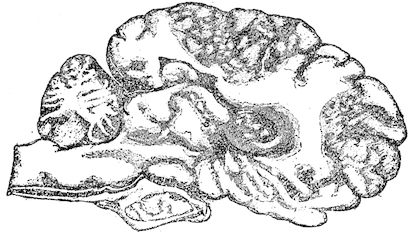

Fig. 8.—Transverse section through the middle region of the face in a pig suffering from osseous cachexia.

18In the final stages, the bones may be cut with a knife, and a time arrives when bony tissue seems completely to have disappeared; thus, as shown in Fig. 8 herewith, it was possible to cut the entire head of a pig into thin slices without the slightest difficulty. All parts of the head had been affected by the softening change.

From the chemical point of view, the diminution in mineral salts and in phosphate of calcium has long been recognised, but the degree of this change varies according to the phase. In human beings the proportions have been estimated as follows: Normal bone, 50 to 80 per cent. of phosphate of calcium; bone in persons suffering from osteomalacia, 5 to 20 per cent. of phosphate of calcium. The changes in the ossein have not been carefully studied. We only know that histologically the ossein becomes fibrillar, and that chemically it no longer retains its normal composition.

Lesions. The chief lesions are to be found in the bones. They consist in rarefaction of the compact tissue, increase in size of the medullary cavity and Haversian canals, and enlargement of the areolæ of the spongy tissue. The bone marrow loses its fatty constituents, appears red and gelatinous, and contains a greatly exaggerated number of blood-vessels. When heated, the bones do not yield oil as in healthy subjects, and when dry, they seem abnormally porous. In the osteoclastic phase, the bones become very friable and even the shafts assume 17a spongy appearance. They diminish in density. These changes correspond to the stages of eccentric rarefying ostitis and osteoporosis of German authors.

The flat bones often show well-marked periostitis, but the great thickening sometimes seen in certain of the bones of the head appears to be the result of a special osteo-periostitis. It is quite certain that the disease is due to something more than a mere want of mineral constituents in the bone, and poverty in this respect certainly does not explain the hypertrophic changes. The nutrition of the bones as a whole is disturbed, resulting in alterations both in the ossein and in the mineral salts, the whole process being accompanied by symptoms of osteo-periostitis.

The fractures which occur so frequently during the osteoclastic phase have well-marked peculiarities. The extravasation of blood is trifling, and no callus forms, even when the ends of the bones are immobilised by external aid; if the ends are left free, they soon become worn and polished by rubbing against one another.

In the neighbourhood of the articulations and ligamentous insertions the periosteum soon undergoes change, and it is not uncommon to find sub-periosteal and intra-osseous extravasations of blood.

Germain has also noted in horses the disappearance of the intervertebral and articular cartilages, and the frequent occurrence of anchylosis, true or false.